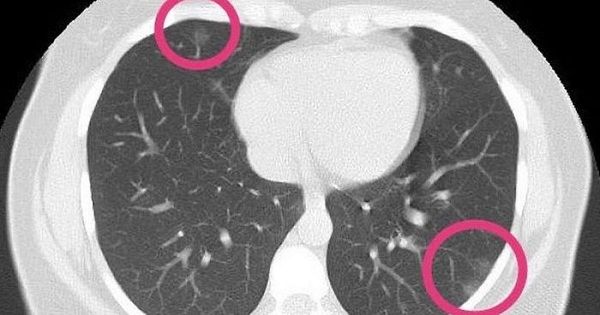

Scan finds coronavirus in lungs of healthy woman, 30, with no symptoms

The worried woman went to a hospital and asked to be tested for coronavirus after a relative died of Covid-19, and two days later she was being treated in hospital for the killer bug